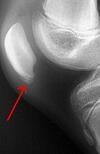

A

avulsion fracture of the fibula (arcuate fracture ) or femoral condyle